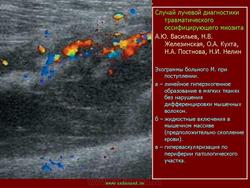

Оссифицирующий миозит

Оссифицирующий миозит